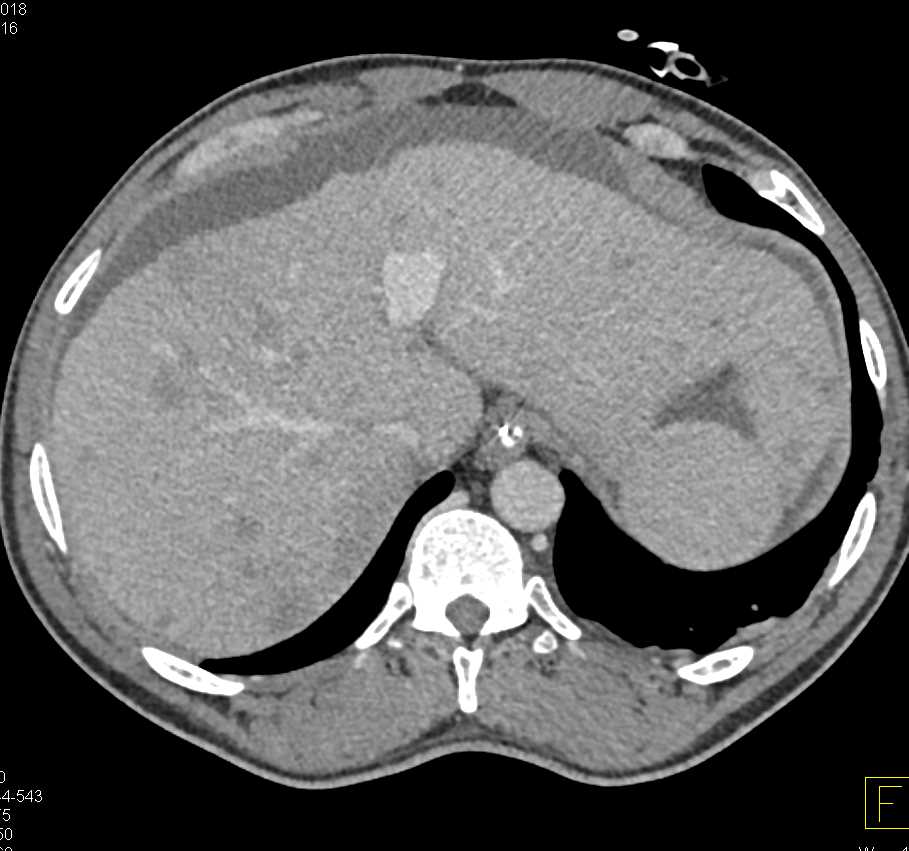

Small Bowel Carcinoma with Carcinomatosis